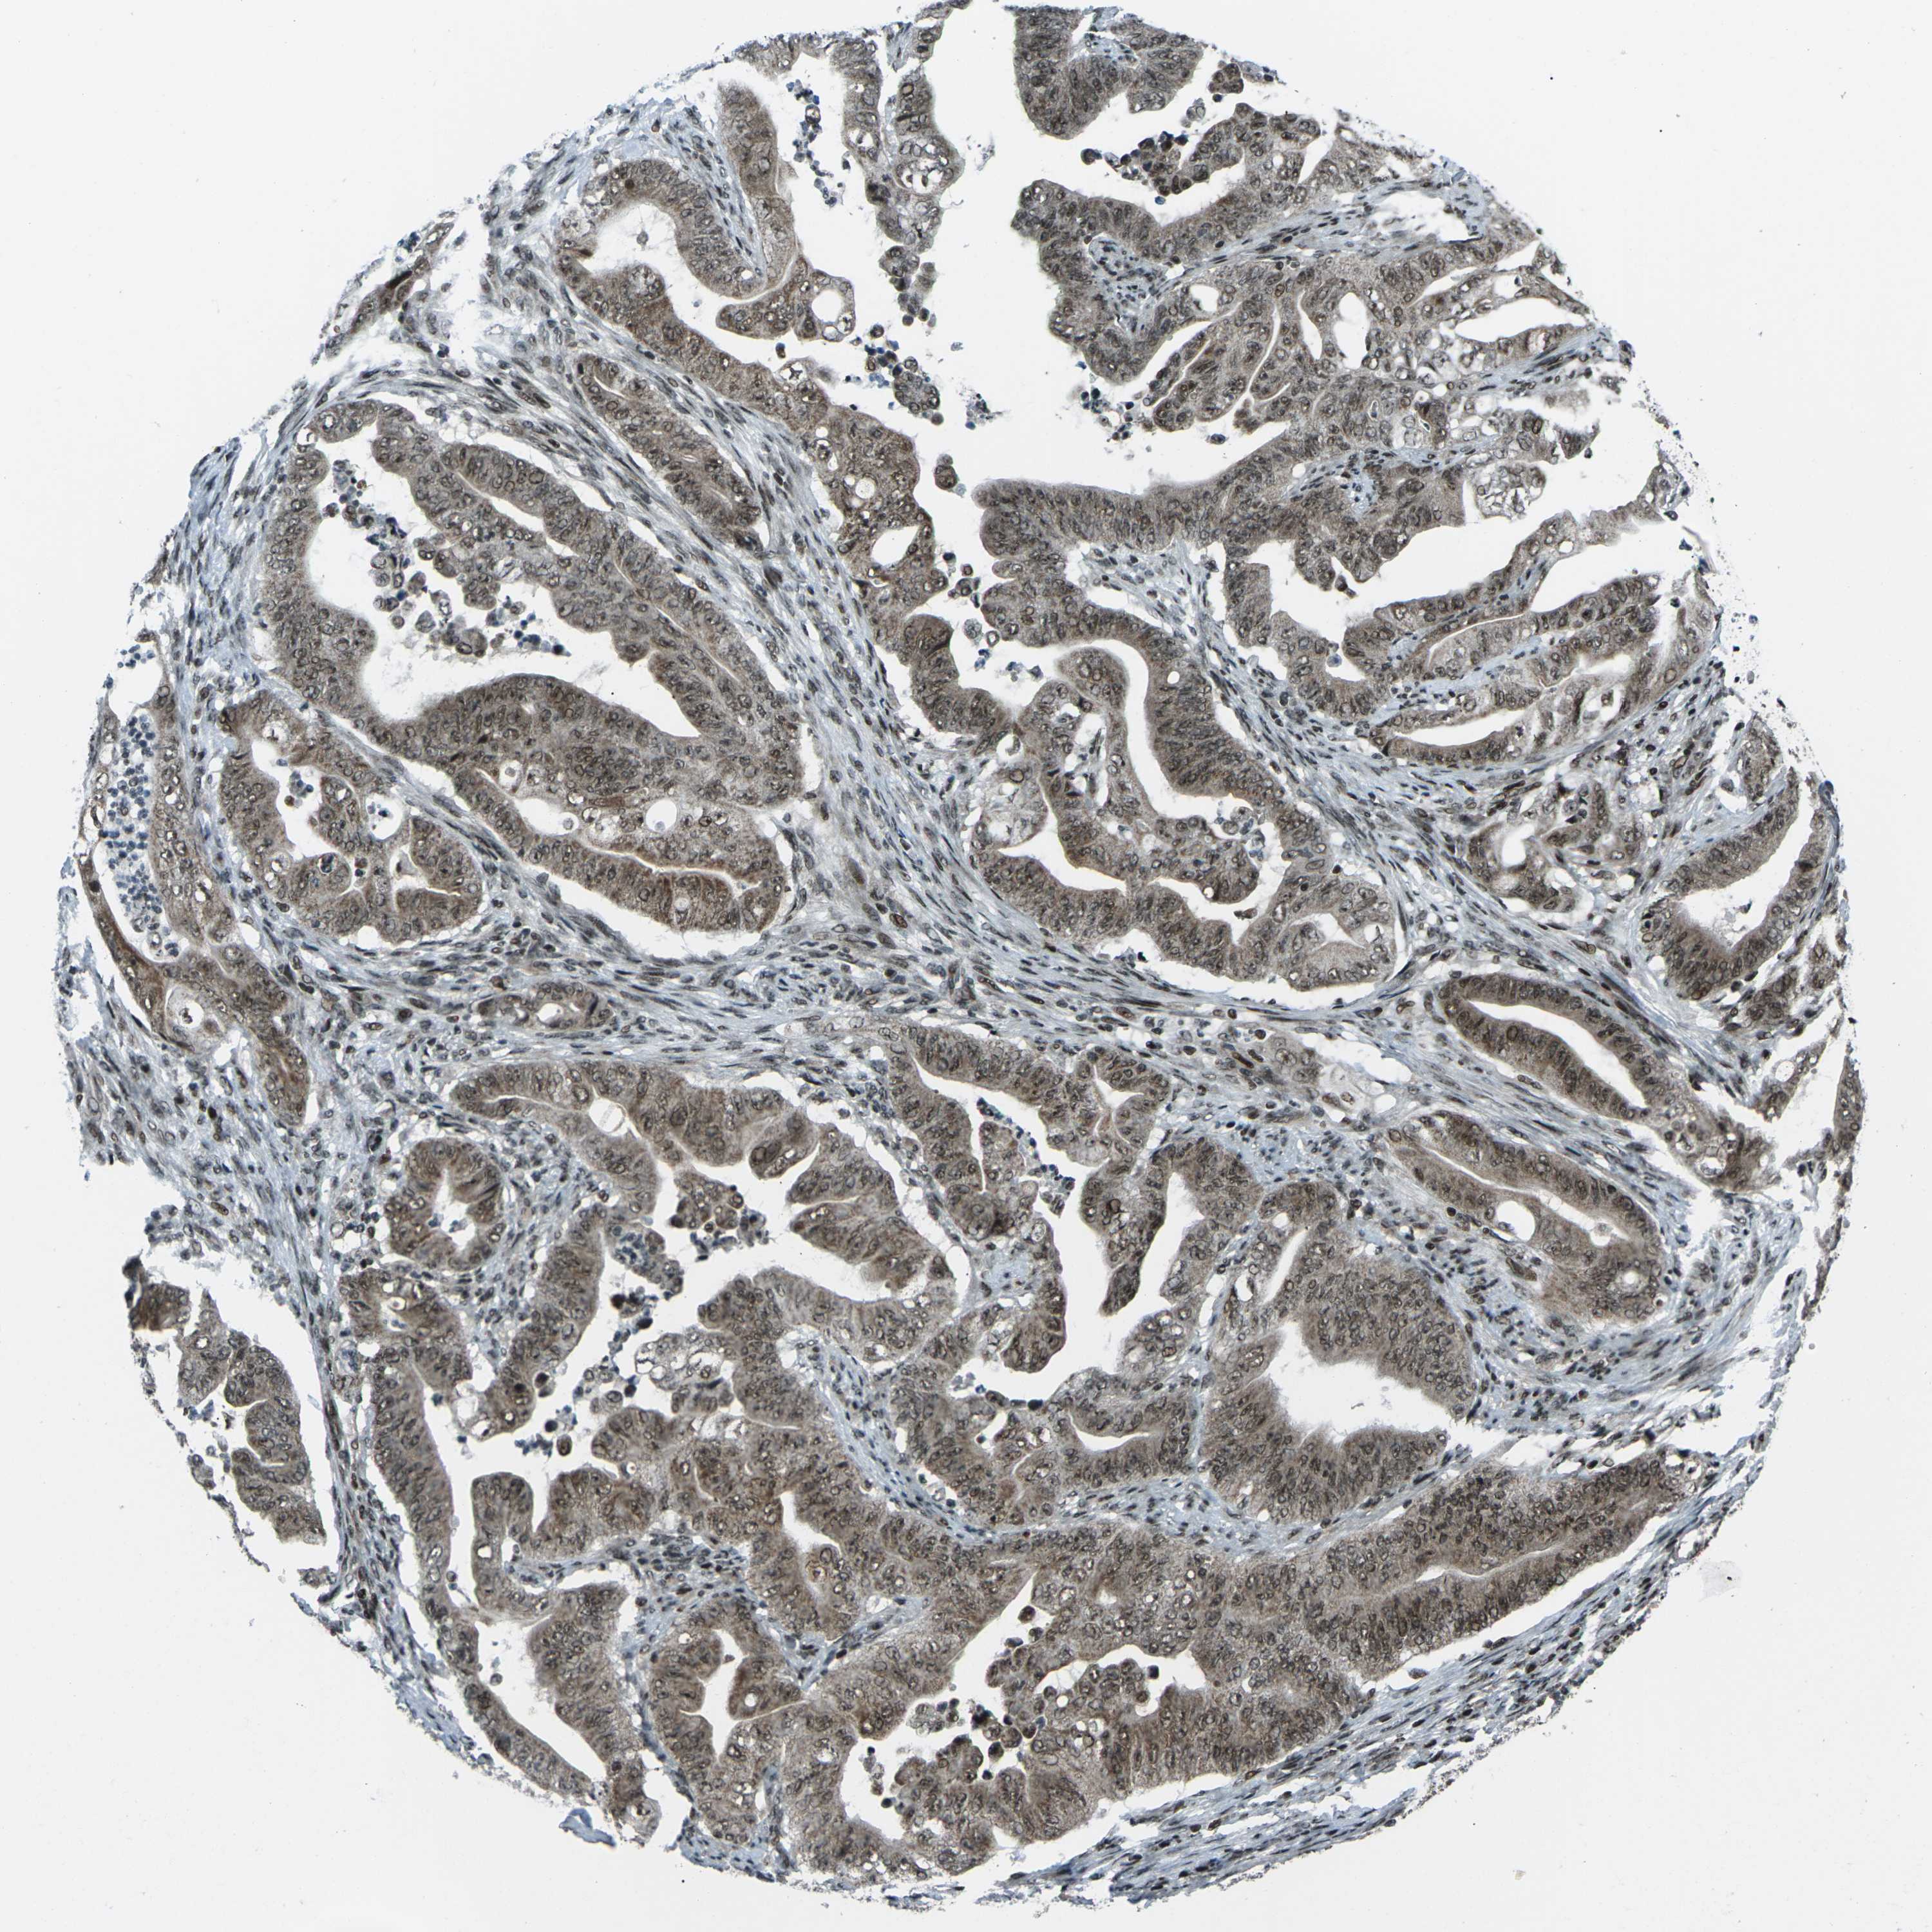

STOMACH CANCER - Protein expressioni

A mouse-over function shows sample information and annotation data. Click on an image to view it in a full screen mode. Samples can be filtered based on level of antibody staining by selecting one or several of the following categories: high, medium, low and not detected. The assay and annotation is described here.

Note that samples used for immunohistochemistry by the Human Protein Atlas do not correspond to samples in the TCGA dataset.

Antibody stainingi

Antibody staining in the annotated cell types in the current human tissue is reported as not detected, low, medium, or high, based on conventional immunohistochemistry profiling in selected tissues. This score is based on the combination of the staining intensity and fraction of stained cells.

Each image is clickable and will lead to virtual microscopy that enables deeper exploration of all samples and also displays staining intensity scores, fraction scores and subcellular localization as well as patient and tissue information for each sample.

Antibody CAB012272

Staining

High

Medium

Low

Not detected

Intensity

Strong

Moderate

Weak

Negative

Quantity

>75%

75%-25%

<25%

None

Location

Nuclear

Cytoplasmic/membranous

Cytoplasmic/membranous,nuclear

Adenocarcinoma, NOS

Adenocarcinoma, High grade